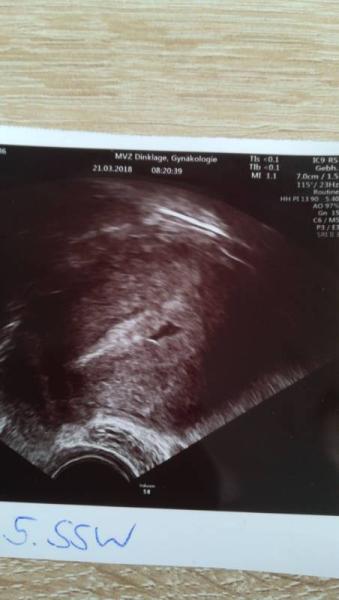

Hallo Mädels! Heute war mein erster Termin bei meiner Gyn Bin heute bei 4+1.ich weiß sehr sehr früh,aber die wollten lieber trotzdem schauen ob alles okay ist.Man sieht nur die Fruchthöhle,aber ist für den Zeitpunkt völlig normal sagte sie. Hoffentlich entwickelt es sich auch schön fleißig weiter.Am 5.4. hab ich meinen nächsten Termin und hoffe das ich dann das süße Würmchen mit sehen kann

Bild zu 1. Termin - Schwanger - wer noch? Rund um die Schwangerschaft

Es wird ein Delphin!! Alles Gute Euch zweien!

Die Form von der Fruchthöhle ;-)

Stimmt, die Fruchthöhle sieht tatsächlich aus wie ein Delphin...

Herzlichen Glückwunsch. Wow da sieht man aber schon viel für die Woche. So sah das bei mir in der 6. Woche aus.